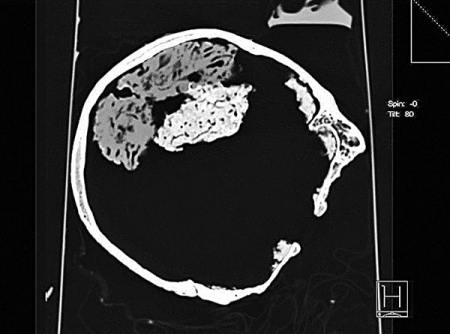

Khi bác sỹ của trường Đại học Sheffield đang chẩn đoán một căn bệnh nhỏ của một học sinh toán, ông bất ngờ phát hiện đầu của cậu bé hơi to hơn bình thường nên bác sỹ của trường đã giới thiệu cậu với Giáo sư Lorber để kiểm tra thêm. Cậu học sinh này có điểm số xuất sắc và chỉ số IQ là 126. Khi Giáo sư Lorber kiểm tra đầu cậu bằng máy quét CAT, ông rất ngạc nhiên khi phát hiện ra cậu học sinh này không có não! Tên của học sinh không được tiết lộ trong bài báo vì bệnh trạng được xem là vấn đề riêng tư ở phương Tây.

Bên trái và bên phải khoang sọ của người bình thường chứa hai vỏ não (thường được gọi là tủy não) trông giống như đậu phụ tròn màu hồng, được cấu tạo từ chất xám và chất trắng, và có nhiều rãnh. Vỏ não thường dày 4,5cm và nối với tủy sống qua hạch nền. Học sinh này có mô não dày chưa đến 1mm bao phủ phần trên cột sống, khoang sọ chứa đầy tràn dịch não (bệnh não úng thủy). Trong hoàn cảnh bình thường, người bị bệnh não úng thủy khó có thể sống sót, thậm chí nếu sống sót cũng sẽ bị tàn tật nghiêm trọng. Tuy nhiên, học sinh đứng đầu khoa toán trước mặt này lại sống một cuộc sống rất bình thường.

Trong mắt giáo sư Lorber, những trường hợp như vậy tuy đặc biệt nhưng không hề hiếm gặp. Bởi chỉ riêng ông đã xác định được hàng trăm trường hợp “người không não” có bán cầu não rất nhỏ, trí lực bình thường và không có sự khác biệt trong cuộc sống, học tập so với người bình thường. Ông mô tả những người này có “bộ não vô hình”.